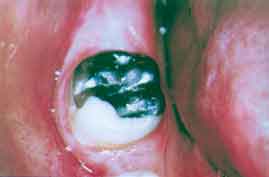

1 ) Paciente do sexo feminino, de 25 anos de idade, molar inferior direito

portador de extensa lesão cariosa, com exposição

pulpar e pequena hiperplasia desse tecido. O paciente relatou haver dores

provocadas e ocasionais surtos de dor expontânea (Figura 1 ).

Figura

1 - Segundo molar inferior direito com extensa lesão

cariosa e

exposição da polpa

dental, que exibe pequena hiperplasia.